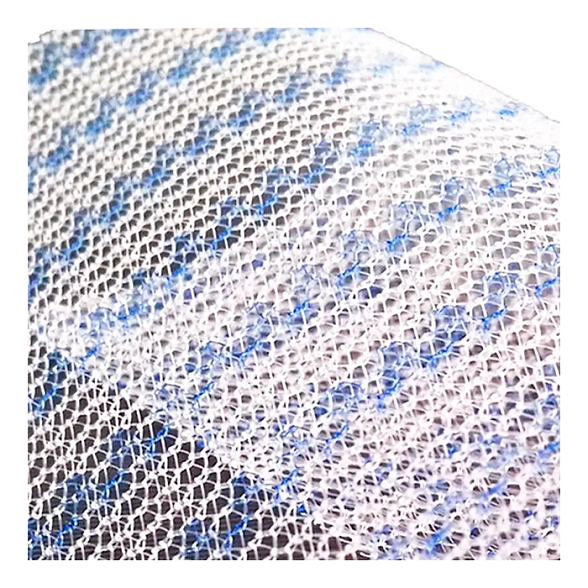

Эндопротез-сетка (сетка хирургическая) полипропиленовый для восстановительной хирургии ЭСФИЛ лёгкий, 15х10 см, Линтекс

Эндопротез-сетка полипропиленовая ЭСФИЛ лёгкий для восстановительной хирургии

Полипропиленовая хирургическая сетка ЭСФИЛ лёгкий от компании «Линтекс» — это современный высокотехнологичный имплантат, предназначенный для надежного и долговечного восстановления анатомических структур при пластических и реконструктивных операциях. Изделие специально разработано для хирургов, ценящих в работе баланс между прочностью, биосовместимостью и комфортом пациента в послеоперационном периоде.

Сетка ЭСФИЛ лёгкий представляет собой монофиламентное полипропиленовое полотно с облегченной структурой. Её ключевая особенность — оптимальное соотношение массы и прочности, что минимизирует реакцию тканей и способствует быстрой интеграции, обеспечивая при этом надежную механическую поддержку на весь срок службы.

- Облегченная структура. Сниженная плотность полимера и площадь контакта с тканями способствует формированию более мягкого и эластичного рубца, уменьшает ощущение инородного тела у пациента.

- Оптимальная пористость. Структура сетки способствует активному прорастанию соединительной ткани (фиброзной инкорпорации), что обеспечивает ее надежную фиксацию в организме и устойчивость к инфекциям.

| Тип структуры | Макропористая, облегченная (low-weight) |

| Поверхность | Не покрытая, макропористая |

Благодаря макропористой структуре, волокна сетки быстро прорастают соединительной тканью (коллагеновыми волокнами). Этот процесс, называемый инкорпорацией, прочно фиксирует имплантат, делая его частью анатомических структур.